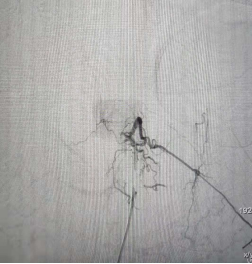

术后造影未见瘘口